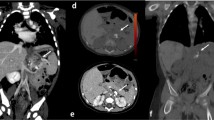

Parameters for the estimation of image quality were defined according to guidelines EUR16262 EN and were used in the analysis of various anatomical structures of the chest: the thoracic wall, mediastinum, trachea, mousse parenchyma and principal bronchi.

In this study, a double-stimulation method\DS\ was used. The observer, a thoracic radiologist, was provided in a blinded manner with the original and the optimized image being tested.

The average image quality grade before and after the optimization was compared. A Mann Whitney U test showed no significant improvement (z = −2.408, p = 0.016), but no significant reduction in image quality after optimization of the CT thorax exam protocol. The image quality rating range before optimization was 3.20 to 4.70, while the median was 3.90. After optimization, the median image quality rating was 4.20, and the image quality rating ranged from 3.20 to 5.00 (Fig. 3).